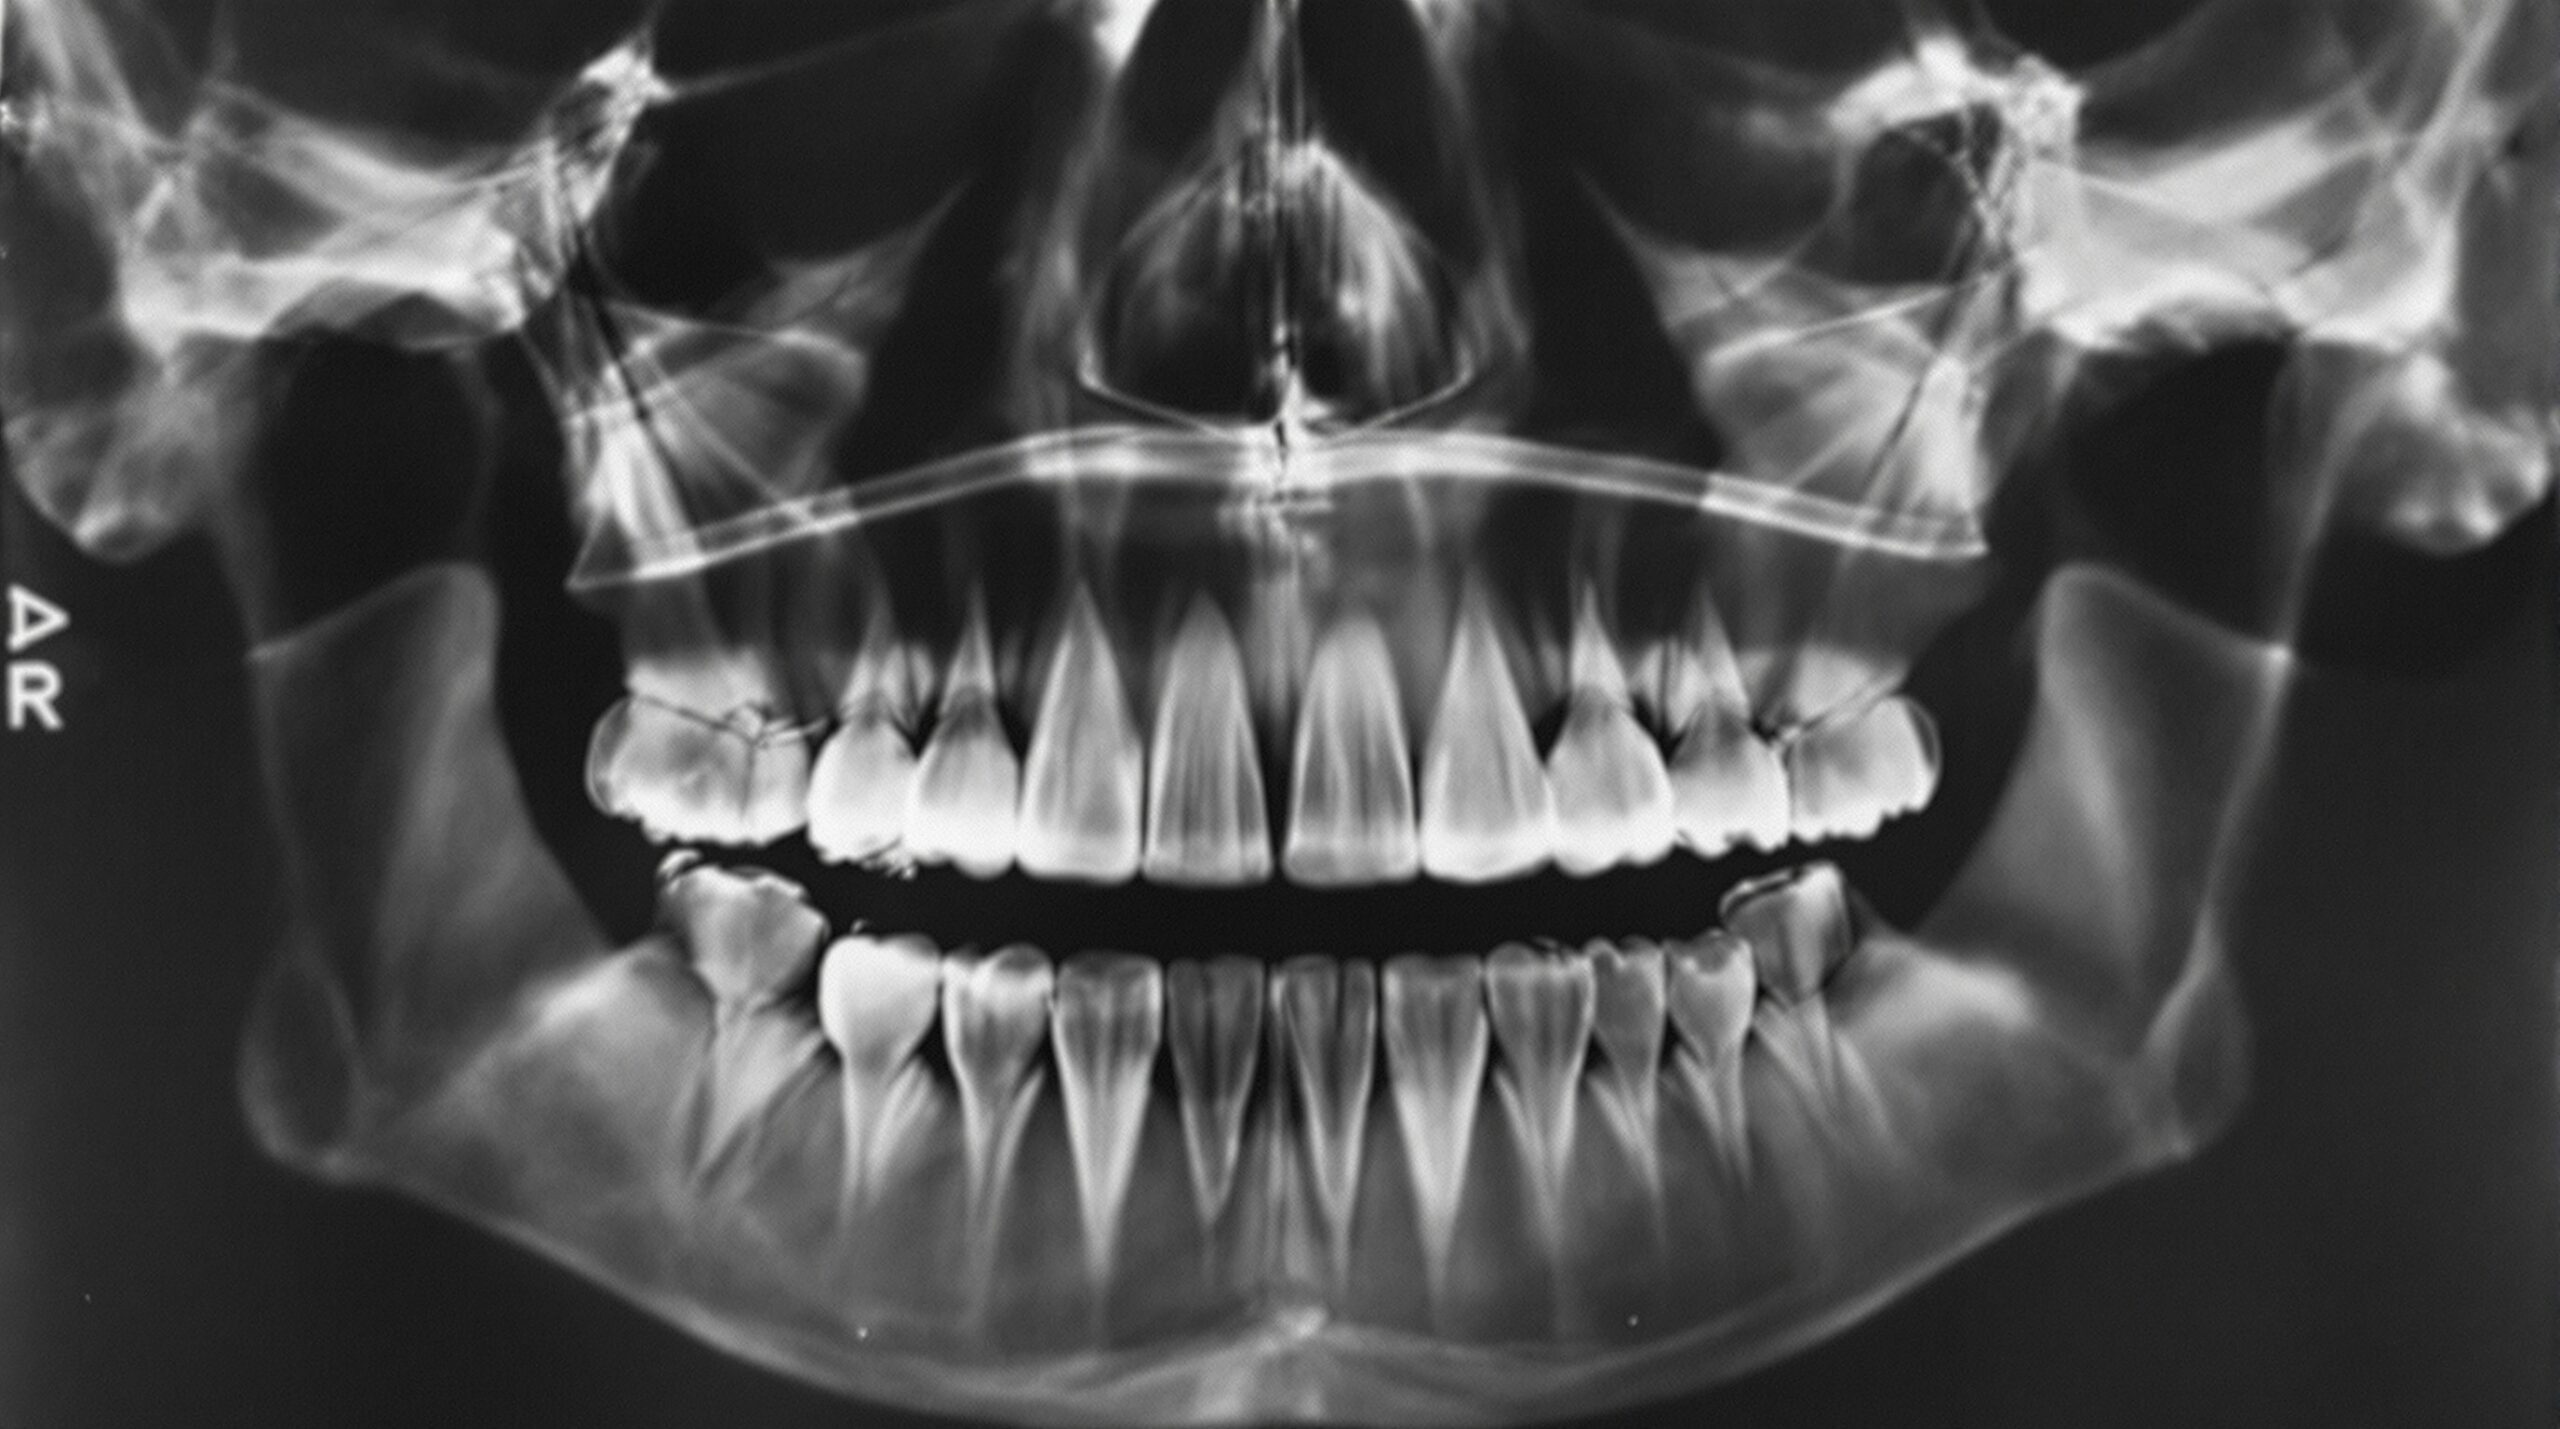

The mid-20th century brought two transformative developments to dental radiography: panoramic imaging and radiation safety standards. In 1949, Finnish researcher Yrjö Paatero developed the concept of panoramic radiography, which could capture the entire jaw in a single image. By the 1960s, commercial panoramic X-ray machines were becoming available in dental offices, offering a comprehensive view of all teeth, the jawbones, sinuses, and temporomandibular joints in one exposure.

CBCT has transformed treatment planning for dental implants, allowing clinicians to precisely measure bone height, width, and density before surgery. It has revolutionized endodontics by revealing root canal anatomy in three dimensions. Orthodontists use CBCT to evaluate impacted teeth and airway dimensions. Oral surgeons rely on it for precise localization of pathology relative to vital structures like the inferior alveolar nerve.